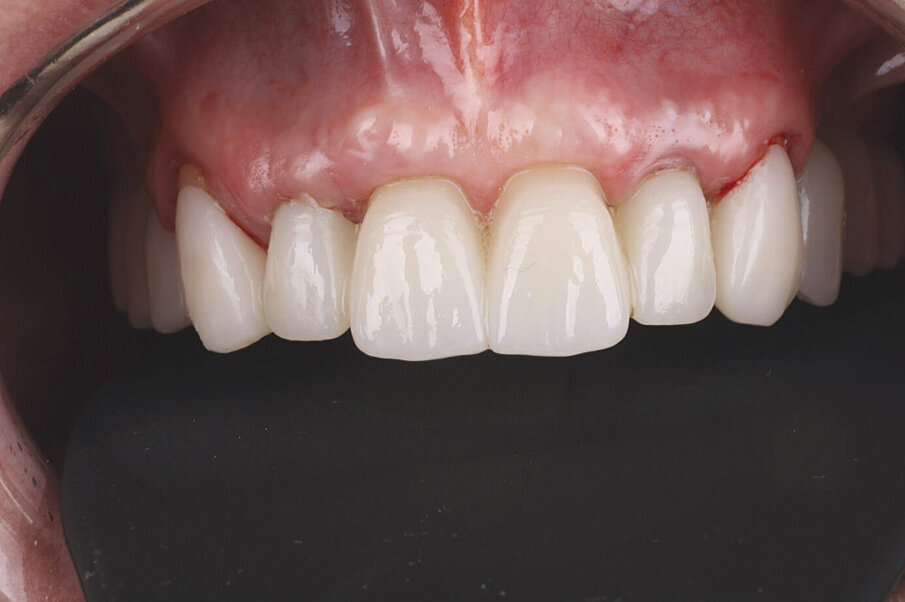

Slika 14. Frontalni prikaz definitivne protetske nadogradnje. Odnosi pokazuju dobru estetiku bez znakova komplikacija mekih tkiva Slika 15. Pogled na definitivni rad s desne strane. Slika 16. Pogled na definitivni rad s lijeve strane. Slika 17. Završna rendgenska slika s definitivnim implanto protetskim radom in situ. Slika 18. Frontalni prikaz definitivnog protetskog rada nakon dvogodišnjeg praćenja. Slika 19. Prikaz definitivnog protetskog rada s lijeve strane nakon dvogodišnjeg praćenja. Slika 20. Prikaz definitivnog protetskog rada s desne strane nakon dvogodišnjeg praćenja.

Definitivni protetski rad napravljen je nakon što je završila faza oseointegracije implantata s tri monolitna mosta od cirkonijevog dioksida (DD CubeX, Dental Direkt) proizvedenih CAD/CAM postupkom. Mostovi su pomoću vijaka pričvršćeni na titanske abutmente (PS TiB, BEGO Implant Systems) (Slike 14–16). Pravilan dosjed protetske nadogradnja se nakon umetanja potvrdio rendgenskom snimkom (Slika 17.). Kontrolni pregled nakon dvije godine u srpnju 2019. pokazao je izvrsno estetsko i kliničko stanje mekog tkiva (Slike 18–20). U području implantata radiografski se nije mogao utvrditi gubitak krestalne kosti (Slika 21.). Oba korijena središnjih sjekutića koji su ostavljeni u alveoli kao ni distobukalni korijen zuba 26 nisu pokazali nikakve znakove periapikalne upale. Pacijentica nije imala nikakvih pritužbi, a oralna higijena značajno se poboljšala tijekom razdoblja praćenja.